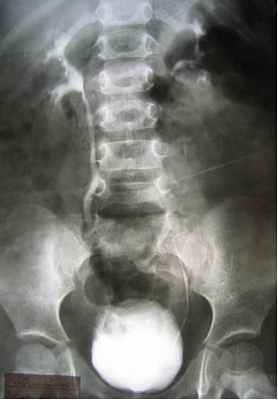

Заподозрить наличие ПМР можно данным УЗС, причём достоверность данных возрастает при использовании допплерографии (рис. 1), но наибольшей информативностью обладает рентгенологический метод - микционная цистография (рис.2). При цистографии контрастное вещество по тонкому катетеру, безболезненно вводится в мочевой пузырь и на рентгеновских снимках, выполненных в покое и при мочеиспускании отчётливо определяется проникновение контрастного вещества в мочеточники и в полостную систему почки (чашечно-лоханочную систему). Дальнейший план обследования зависит от выявленной патологии и может включать: лабораторное обследование, экскреторную урография, статическую и динамическую сцинтиграфию почек, уректро-цистоскопию, уродинамическое обследование, консультация невролога.